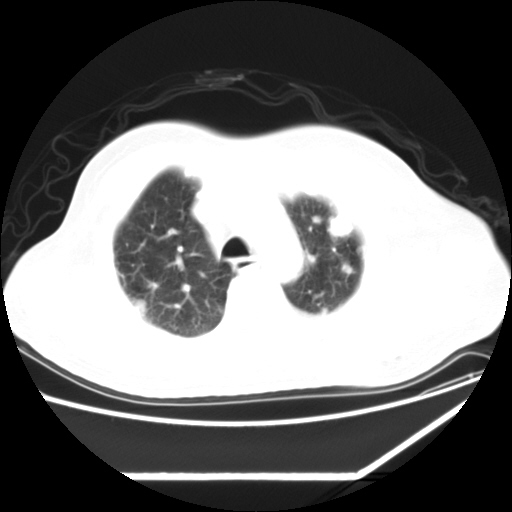

男,57,畏寒,发热

双肺多发结节样病灶,部分内见透光区,纵隔内见淋巴结肿大。结核临床如有畏寒,高热,白细胞增高首先考虑迁徙性肺脓肿(多是金黄色葡萄球菌感染)。

注意除外转移瘤。

血源性肺脓肿

血源性肺脓肿,除外转移瘤

肺多发结节样病灶,部分内见透光区,纵隔内见淋巴结肿大。结核临床如有畏寒,高热,白细胞增高首先考虑迁徙性肺脓肿(多是金黄色葡萄球菌感染)。